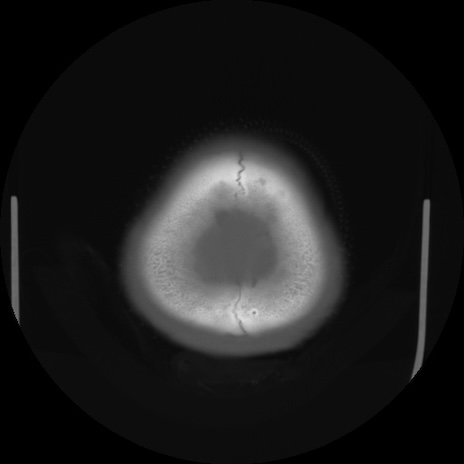

【頭部】症例5 CT(横断像)

CT(冠状断像)

【症例】80歳代 男性

【主訴】頭部打撲

【現病歴】外出先で椅子から立ち上がる際に、つまづいて後方へ転倒し受傷。転倒時に意識はあった。

【身体所見】BP 217/71、HR 96、JCS1-1、 難聴あり、顔色良好、右後頭部に擦過創あり。神経学的異常なし。

症例5の画像所見と診断は?